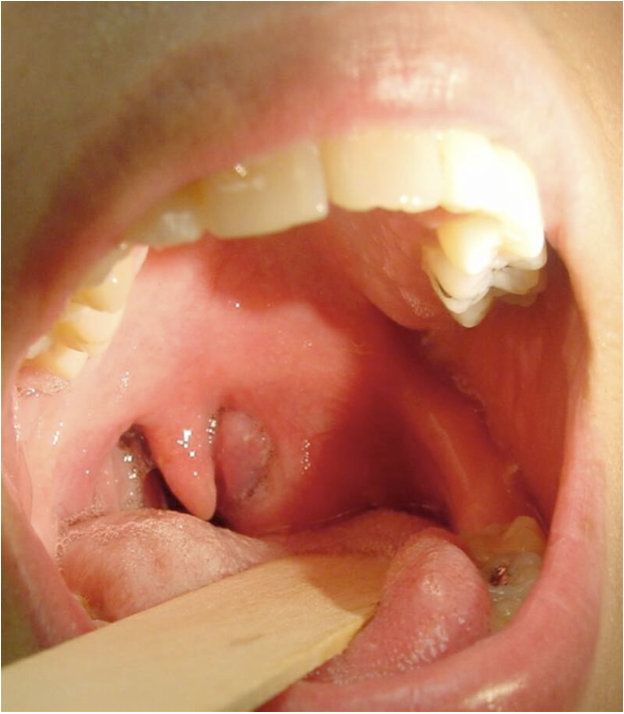

- grayish green plaques friable membrane